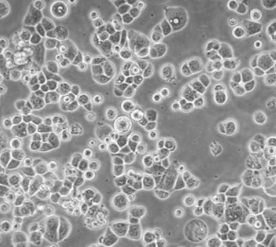

2. 细胞名称:ZR-75-30(人乳腺癌细胞)

7. 细胞类型:上皮细胞样

8. 生长特性:贴壁生长